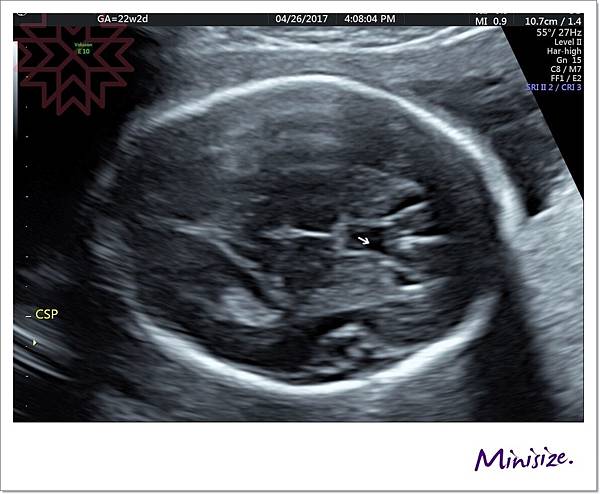

腦

箭頭處為透明中膈要明顯

左右腦也要對稱